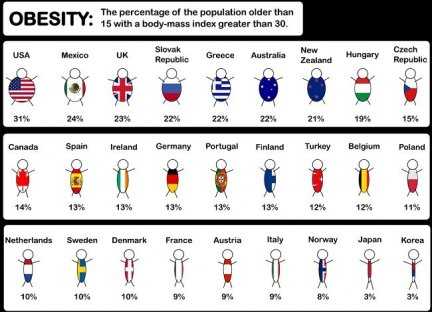

23 miliardi invece, sono lenorme cifra spesa in Italia, sempre ogni anno, per curare o meglio, tentare di curare lobesità, patologia sempre più diffusa anche fra i giovani.

23 miliardi invece, sono lenorme cifra spesa in Italia, sempre ogni anno, per curare o meglio, tentare di curare lobesità, patologia sempre più diffusa anche fra i giovani.